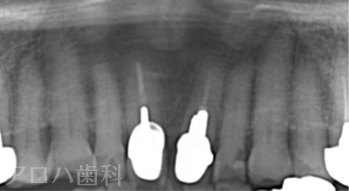

CASE01/50代男性

| 主訴 | 左の奥歯が噛めない |

| 治療内容 | 下顎臼歯3歯欠損をインプラントで修復しました。 デジタル機器を使いコンピュータで理想的な歯の形態を設計。 歯ぐきに隙間が出来る事なく修復できました。 |

| 治療期間 | 3ヶ月 |

| 治療費用 | 1,375,000円 |

| 費用詳細 | ・サージカルガイド 55,000円 ・GBR 110,000円 ・インプラント手術+アバットメント+上部構造(3歯) 1,320,000円 |